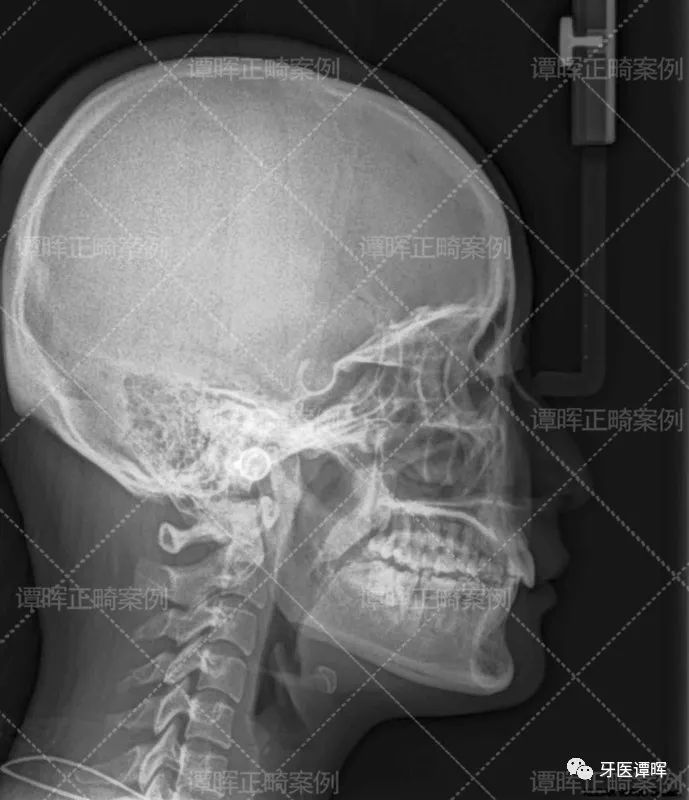

从X线分析图可以明显看出前牙往前突内收,上牙的侧切牙也已排齐,牙列排齐。

从前的她不敢大笑,而且笑起来总是不自然,但现在的她敢露牙大笑。不仅门牙排列整齐,正面微笑脸型也更加柔和了。